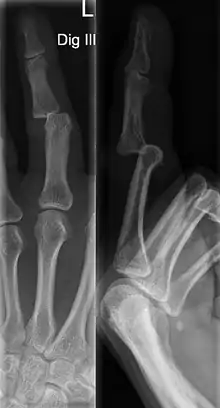

A jammed finger can generally be diagnosed via physical examination. The relative position of the bones of the finger give an indication as to potential dislocations or fractures.[3] However, it is recommended to seek medical attention regardless of whether or not a dislocation or fracture is evident.[6] This is because untreated jammed fingers can lead to future pain and stiffness, with joint surface fractures increasing the risk of arthritis.[6] The areas around the injury may be palpated in order to ascertain the areas of maximum pain.[2] If the injury is a joint injury (namely a sprain or dislocation), the point of maximum pain will be close to the joint rather than mid-phalanx (mid-bone).[2] Due to the risk of dislocations or fractures, stability testing is not recommended until after an x-ray has been conducted and the presence of a dislocation or fracture has been confirmed or rejected.[2] In extremely painful cases, a digital nerve block, where anaesthetic is injected in the web to either side of the affected finger, may be employed to enable assessment of the injury.[2] X-rays may be employed to achieve a more accurate diagnosis of a jammed finger, enabling the identification of varying types of dislocation or fractures. In order to account for all possibilities, it is recommended that a variety of views (lateral, oblique, and anteroposterior) are observed.[2]

Dislocations can be categorised based on location and type. The finger can be split into three bones and two joints in an alternating order. From the fingertip to the knuckle, these are as follows; distal phalanx, distal inter-phalangeal (DIP) joint, middle phalanx, proximal inter-phalangeal (PIP) joint, and proximal phalanx. DIP dislocations are much less common than PIP dislocations,[2] due to the “stability provided by strong collateral ligaments, palmar plates, and tendinous insertions, as well as the short lever arm of the distal phalanx”.[7] Dislocations can be categorised based on the direction that the fingertip moves in relation to the knuckle, be it in the direction of the palm (volar dislocation), or the direction of the back of the hand (dorsal dislocation). Of the two, dorsal dislocations are more common.[3] If reduction has been attempted, an x-ray of the dislocation should appear concentric if successful.[2] However, if there is a fracture present, there will be a misalignment of the joint, which will be evident from the radiograph.[2] Bach suggests a referral to a hand surgeon if a misalignment is present.[2]

Fractures are instances where the bone's structural integrity has been compromised. This is indicated by midshaft pain, as well as visual midshaft angulation or rotation.[3] As with any skeletal injury, an x-ray can be conducted to verify the presence of a fracture.[1] The distal phalanx is especially vulnerable to avulsion fractures, where a fragment of bone is ripped off when the tendon separates from the phalanx.[1] Avulsion fractures are especially common following a first time dislocation.[1] These are especially concerning, as it may indicate a complete tear of the extensor digitorum tendon. If left untreated, this may lead to permanent DIP extensor lag (inability to fully straighten the finger).[8]